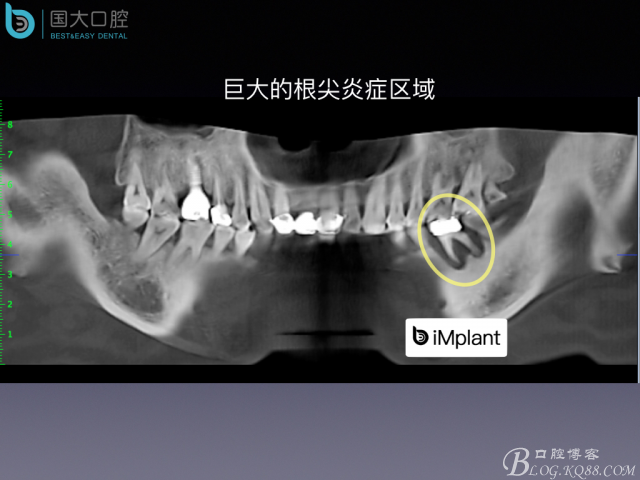

嚴(yán)重根尖周炎能做即刻種植嗎?